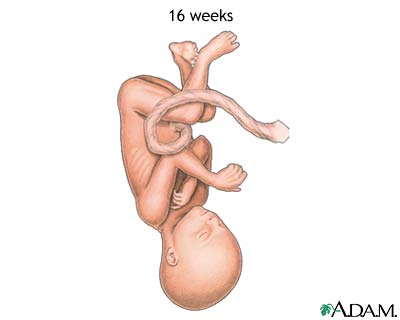

Weeks 15 to 18

- At this stage, your baby's skin is almost transparent.

- Fine hair called lanugo develops on your baby's head.

- Muscle tissue and bones keep developing, and bones become harder.

- Your baby begins to move and stretch.

- The liver and pancreas produce secretions.

- Your little one now makes sucking motions.